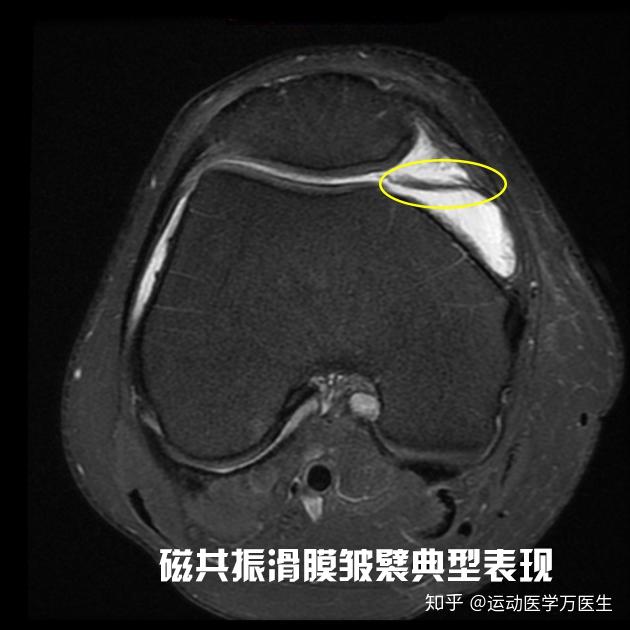

膝关节里那磨人的小妖精:滑膜皱襞(plica)综合症_膝关节损伤_发病原因

病例讲解髌骨内侧滑膜皱襞综合征

卡住的膝关节之三---内侧滑膜皱襞综合征_膝关节损伤_膝关节损伤介绍

时是膝关节内侧痛,经mri和关节镜确诊为内侧半月板损伤,内侧滑膜皱襞

膝关节内多出来一片滑膜皱襞

关节滑膜皱襞症忽隐忽现难确诊_介绍_相关疾病 - 好大夫在线

膝关节疼痛上下楼梯困难要当心膝关节滑膜皱襞综合征

上,下楼梯时膝内侧疼痛?快来检查一下你的滑膜皱襞吧